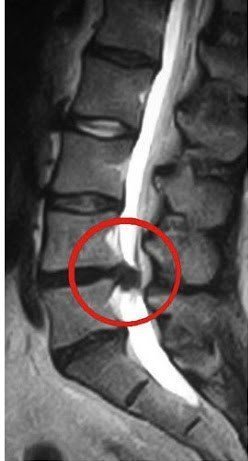

Симптоми міжхребцевої грижі

Ознаки грижі хребта залежать від місця розташування пошкодженого диска. Хребетна грижа поперекового відділу супроводжується болем в нижній частині спини, яка віддає в ногу або сідницю. Можливо відчуття оніміння в ногах. Симптомами хребетної грижі шийного відділу є біль в області голови, шиї, плечей. Хворого турбують запаморочення, підвищений тиск, шум у вухах, оніміння пальців рук. Грижу міжхребцевого диска в грудному відділі можна визначити по болю в області грудей, від якої не рятують серцеві ліки.

Особливості лікування гриж дисків хребта

Світова статистика свідчить, що операції з видалення грижі диска потребують не більше 2% пацієнтів. Наявність грижі, як такої, не є 100% показанням до операції. Не варто поспішати з видаленням грижі. Питання тактики лікування грижі визначає лікар-вертебролог після ретельного неврологічного огляду і аналізу результатів обстеження. Як правило, такі заходи як фізіотерапія, мануальна терапія, витягування, ЛФК та медикаментозна терапія в 98% випадків бувають більш корисні для хворого, ніж хірургічне лікування.